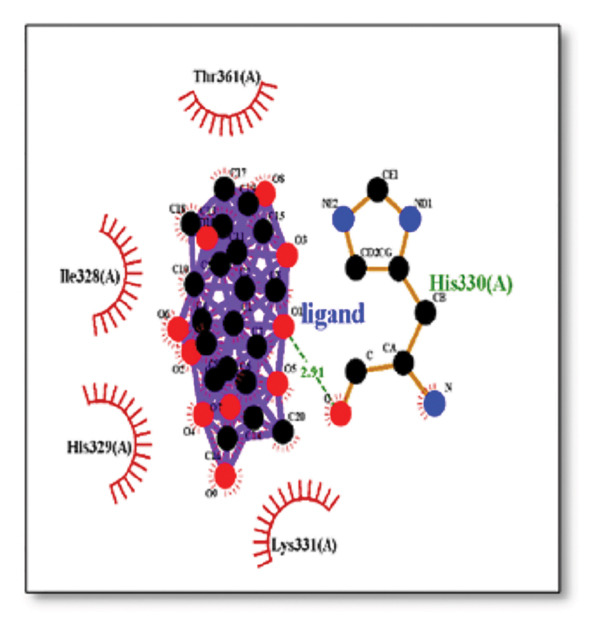

For the tau protein repeat domain, ginkgolide recorded a strong binding energy of −10.63 kcal/mol, with a key stabilizing interaction involving HIS329. This interaction was characterized by a D–A distance of 3.05 Ǻ and an excellent angle of 170.04°. Other top binding compounds included ginsenosides (−6.28 kcal/mol), also interacting with HIS329 and PRO364, and galantamine (−5.47 kcal/mol), forming bonds with VAL337 and VAL339. Berberine bound at −5.33 kcal/mol via GLN351. Apigenin exhibited favorable interaction with the tau repeat domain via a hydrogen bond with ILE 328 (D–A: 2.91 Ǻ; angle 161.21°), highlighting the high quality of the interaction. Among the reference drugs, donepezil bound at −5.34 kcal/mol. Figure 5 details the binding characteristics for tau protein.

Histidine residues are frequently involved in coordinating chaperone‐substrate interactions. The binding of ginkgolide at HIS205 suggests it may stabilize the active conformation of the chaperone, thereby enhancing its ability to bind to and inhibit the formation of amyloid fibrils, a key mechanism reinforced by recent research published [ref. 40]. This research has consistently reinforced that clusterin’s ability to bind to and inhibit the formation of amyloid fibrils is a key mechanism of action, particularly in neurodegenerative diseases. While direct mention of HIS205 is rare, its chaperone function is broadly understood to rely on such key residues. Elias et al. [ref. 41] and Carini et al. [ref. 42] confirm that clusterin’s role in inhibiting aggregation is a major focus of current research. Finally, the predicted binding to HIS329 in tau is highly significant and directly corroborated by recent literature. HIS329 is explicitly located within the microtubule‐binding repeat domain, which is the primary site for tau’s pathological self‐aggregation. Ginkgolide’s predicted binding at this position is a direct mechanism of aggregation inhibition, suggesting it acts as a steric wedge or “capping agent” to prevent the formation of toxic beta sheet structures, aligning with similar strategies explored. Studies have explicitly identified histidine residues within the microtubule‐binding repeat domain as participants in tau’s self‐aggregation process. Hernández et al. [ref. 43] specifically names residues like H329 as being involved in this mechanism. Molecular docking and simulation studies, such as one from 2025 by Saha and Natarajan [ref. 44], also focus on targeting this domain with small molecules to inhibit tau pathology, providing strong support for the in silico predictions.

Abbaoui et al. [ref. 51] conducted an in silico analysis focusing on AD acetylcholinesterase (AChE) as the target protein and examined carnosic acid and related abietane‐type diterpenes from rosemary. Analysis revealed favorable ADME/T profiles and robust binding affinities (−5.560 to −7.270 Kcal/mol) with AChE. Tedeschi et al. [ref. 52] examined garlic and its components in experimental cellular or mouse models of AD. The review highlighted the beneficial antioxidant and neuroprotective anti‐inflammatory properties of allicin and AGE contained in garlic extracts. Apigenin (4,5,7‐trihydroxy flavone) is a natural flavone in fruits, parsley, celery, and chamomile [ref. 53]. Apigenin, a ubiquitous flavonoid, demonstrated favorable binding to sortilin and tau. Apigenin’s interactions with GLY326, VAL363, and ILE328 in Tau are consistent with the known strategies of tau aggregation inhibitors [ref. 54] that target residues within its repeat domain [ref. 55]. Mechanistically, these residues form part of the core aggregation motif, suggesting apigenin functions as a small molecule inhibitor by sterically hindering the $\beta$‐sheet stacking essential for self‐assembly. Studies indicate that it has antioxidant, neuroprotective, anti‐inflammatory, and anti‐Aβ aggregation activities [ref. 56]. More crucially, it can pass the BBB. As per Siddique et al. [ref. 57], apigenin is powerful in lowering the AD symptoms, which are mimicked in the transgenic Drosophila model of AD. It is concluded that apigenin inhibits the activity of acetylcholinesterase and the formation of Aβ‐42 aggregates.